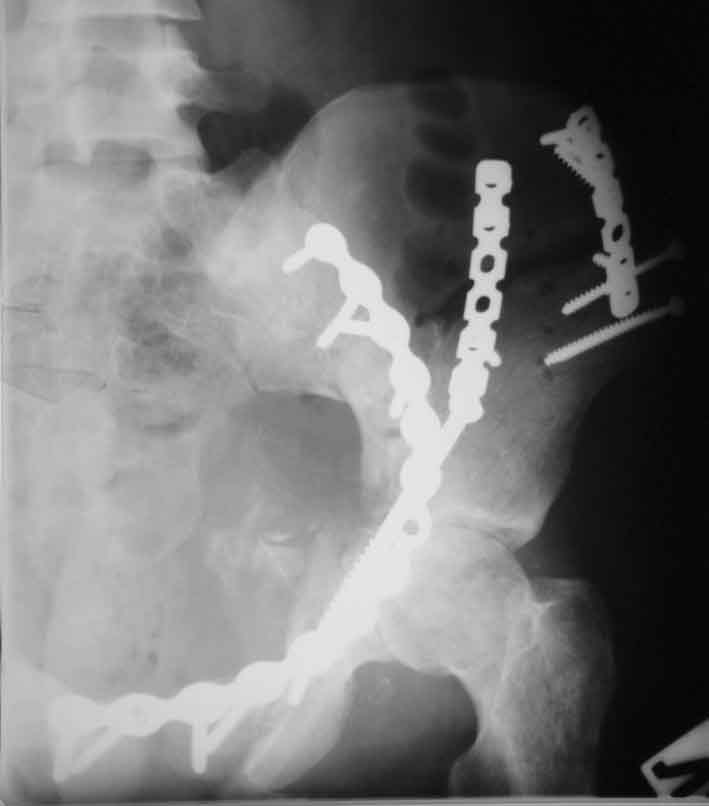

Рентгенограммы после операции

запирательная